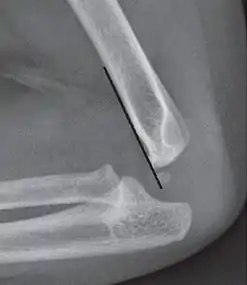

Supracondylar humerus fracture

An elbow X-ray showing a displaced supracondylar fracture in a young child

A supracondylar humerus fracture is a fracture of the distal humerus just above the elbow joint. The fracture is usually transverse or oblique and above the medial and lateral condyles and epicondyles. This fracture pattern is relatively rare in adults, but is the most common type of elbow fracture in children.[1] In children, many of these fractures are non-displaced and can be treated with casting. Some are angulated or displaced and are best treated with surgery. In children, most of these fractures can be treated effectively with expectation for full recovery.[2] Some of these injuries can be complicated by poor healing or by associated blood vessel or nerve injuries with serious complications.